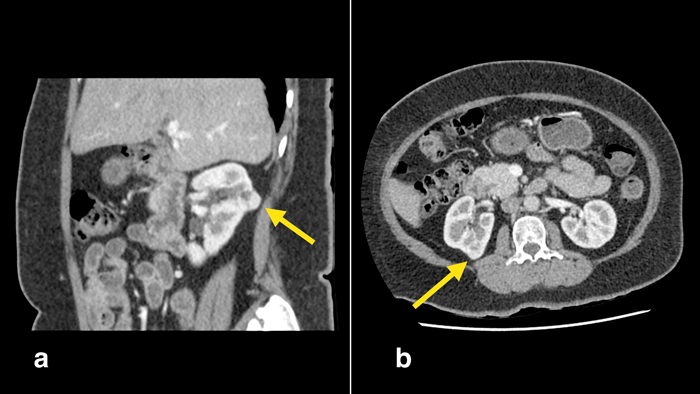

Figure 3: Robotic assisted partial nephrectomy operation. a) Kidney defatted and posterior hilar tumour just visible (yellow arrow). b) Intraoperative robotic ultrasound probe to delineate margin of tumour. c) Tumour margin circumscribed with diathermy. d) Tumour being excised with cold cutting and ‘fracturing’ of the healthy renal tissue.

Robot-assisted partial nephrectomy (RAPN) (Figure 3) utilises the four-arm da-Vinci robot (Intuitive Surgical Inc., Sunnyvale, CA, USA) with a camera port, an assistant port and two 8mm instrument ports. RAPN may be performed through the trans or retroperitoneal route. RAPN is gaining in popularity, and is, now, one of the fastest growing robotic operations in the world in terms of numbers. The robotic system provides 3D imaging and excellent wrist motion (EndoWrist, Intuitive Surgical Inc., Sunnyvale, CA, USA), allowing for better manoeuvrability, particularly in confined spaces. It offers the advantages of LPN while addressing some of the limitations of LPN. This includes a shorter learning curve for RAPN and the elimination of tremor. Furthermore, the robot also allows easier operation on more complex tumours that may be difficult to access or resect with the laparoscopic approach.

This is one of the more interesting developments for partial nephrectomy. LPN and RAPN often employ the use of intraoperative ultrasound (Figure 3b) to identify the tumour, corroborate pre-operative imaging and aid with surgical margins. New imaging methods are constantly being explored to aid surgery. Where selective vascular clamping is appropriate, indocyanine green (ICG) fluorescence imaging [4] has been used to identify tumour and aid selective arterial clamping (Figure 4). ICG is a dye that fluoresces bright green under infrared light. Normal tissue which fluoresces normally is distinguished from tumour which does not fluoresce well. Newer methods of identification such as fluorescence using molecular contrast agents (FRα) [5] have also been reported. Another more cost-effective method is the use of SonoVue bubble contrast-enhanced ultrasound to map renal blood flow and allowing for more accurate selective arterial clamping [6].